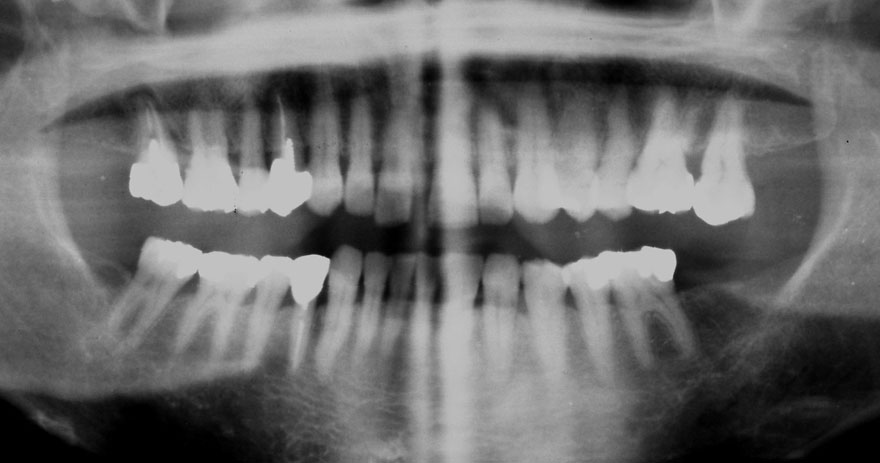

開始年齢 30代

初診時 30歳 女性 平均歯槽骨喪失量:1.46mm

22年後 52歳

平均歯槽骨喪失量:1.55mm

22年間喪失量:-0.09mm

年間喪失速度:-0.004mm

(ケア頻度:1.76ヵ月ごと)